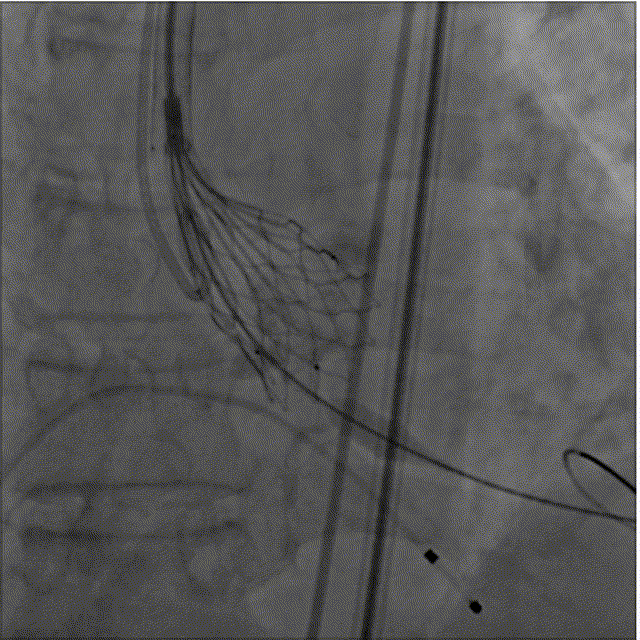

球囊(25mm)预扩钙化的主动脉瓣

SinoCrown瓣膜定位

SinoCrown瓣膜逐步释放